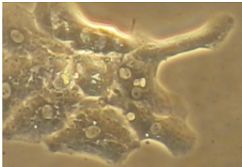

Inflammatory response in glial cells in a 3D organoid model of neurodegeneration